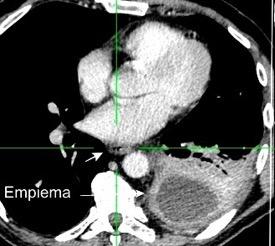

Marzo 2014: Perforación longitudinal distal secundaria a episodio de vómito (síndrome de Boerhaave). Derrame pleural izdo. que evoluciona a empiema.

Wang C-T et al. Tension hydropneumothorax in a Boerhaave syndrome patient: A case report . World J Emerg Med, 2021. Katabathina V et al. Nonvascular, nontraumatic mediastinal emergencies in adults:a comprehensive review of imaging findings. Radiographics. 2011.